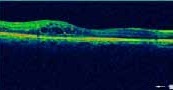

La Tomographie en Cohérence Optique (OCT) L’OCT est indiquée essentiellement dans l’œdème maculaire compliquant les atteintes du segment postérieur (figure 6). Elle permet de mesurer de manière reproductible l’épaisseur maculaire, afin de suivre l’évolution de cet œdème et donc d’adapter les différents traitements (4.5).